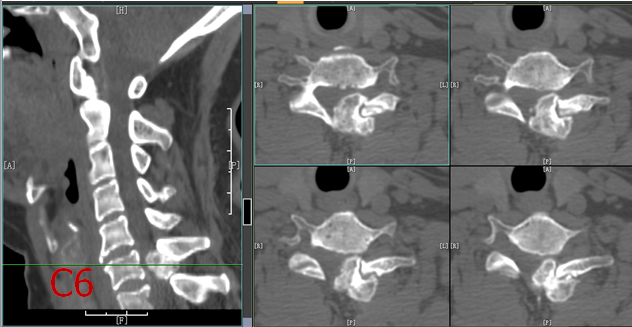

颈椎CT示:C6水平椎管内占位